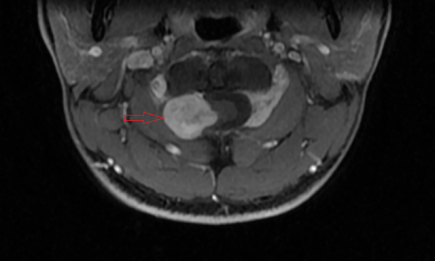

近期,富顺县中医医院脑病科成功为一名脊髓硬膜外神经鞘瘤患者进行手术治疗,为患者解除了长期的病痛折磨。该患者在2年前无诱因出现阵发性双手、双小腿麻木、乏力,偶伴头晕、黑矇等症状,在我院接受颅脑磁共振检查后发现其颈1-2水平脊髓外异常占位,考虑神经鞘瘤(图中红色箭头标注)。